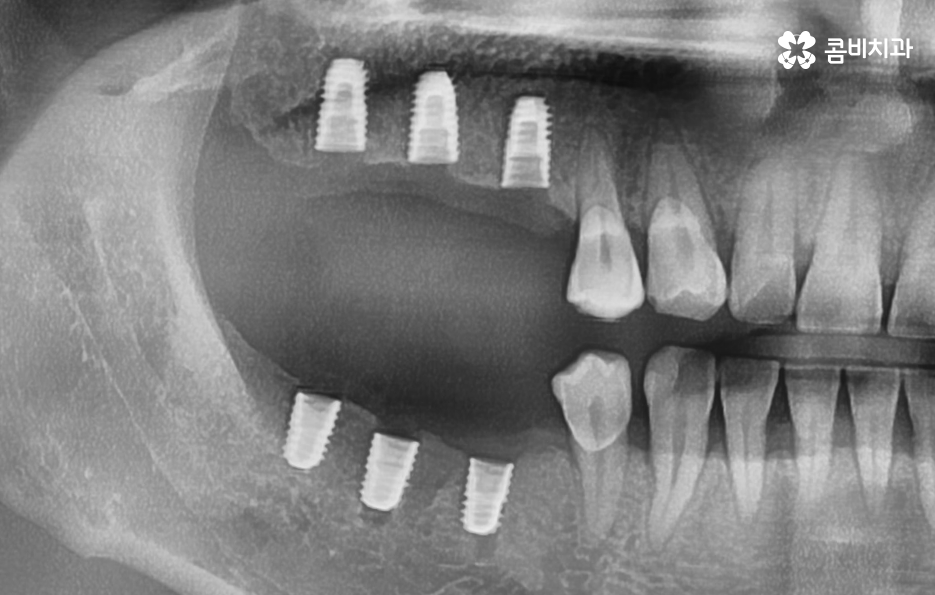

반면에 치주염이 심해져서 치조골이 녹아내리고 이미 치아의 뿌리가 보일 정도로 잇몸이 약해진 상태에는 치아 발치 후 잇몸이 충분히 회복한 뒤 임플란트를 식립할 수 있는 잇몸 뼈가 충분한지 확인 후 경우에 따라서는 뼈이식이 추가될 수 있는데요.

임플란트는 잇몸 뼈에 식립하기 때문에 치주염으로 인해 잇몸 뼈가 부족하거나 치아를 발치 후 오랜 시간이 지난 다음에 임플란트를 하게 될 경우 임플란트를 식립할 충분한 잇몸 뼈의 확보를 위해 뼈이식을 받아야 할 수 있어요

생각보다 많은 40대 환자분들이 충치 외에도 치주염으로 인해 풍치 진단을 받고 치아를 발치하게 되는 사례가 많기 때문에 40대임플란트 치료 과정 중에 잇몸 뼈의 중요성에 대해 설명드려야만 왜 나는 치료 방법이 달라지고 뼈이식을 받아야 하는지 등과 같은 궁금증을 해소할 수 있을 거예요